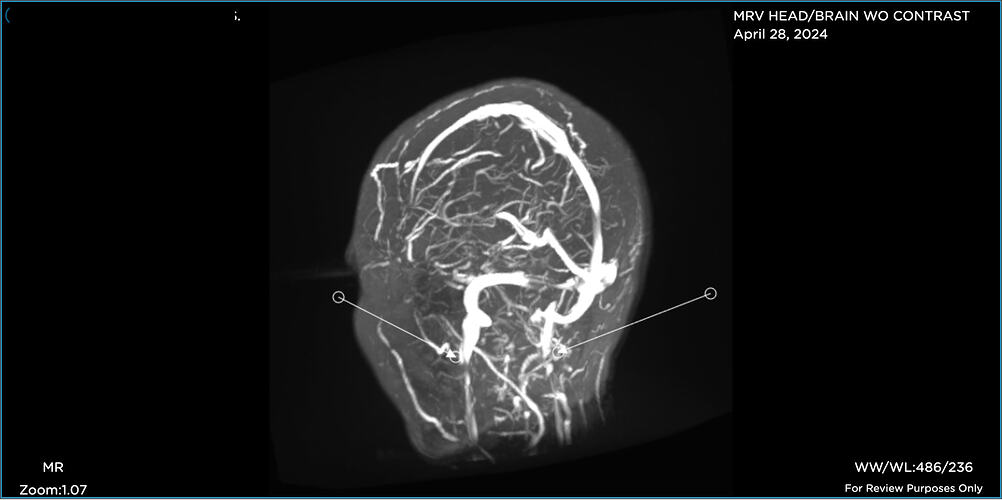

Hi folks. Like many of you, I’ve been on a miserable journey for years now. I’m just diagnosed “officially” with Eagles yet, but my provider said she sees elongated styloids on both sides, and she has referred me to Hepworth and recommends styloidecomy(ies).

Prior to seeing her, I’d been dealing with a CSF leak (5 blood patches to date), chronic migraines, Central Sensitization Syndrome/fibro (basically whole body pain), etc. When my FMC looked at the imaging I finally uploaded, she immediately noticed elongated styloids on both sides and she recommends styloidectomy(ies).